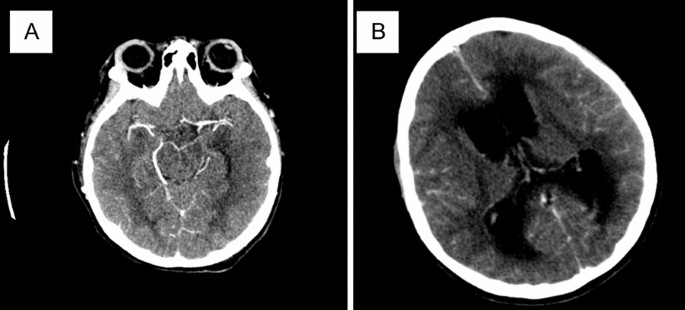

Laboratory results indicated leukocytosis of 1074 × 109/L. Cerebrospinal fluid analysis for leukocytes and protein were elevated, and glucose levels were decreased, indicating bacterial meningitis. The cerebrospinal fluid test revealed negative acid-fast bacilli, and the cerebrospinal fluid culture revealed no growth of microorganisms. Head CT scan revealed hydrocephalus and basal enhancement (Fig. 3). The patient was treated for meningoencephalitis tuberculosis (METB) with antituberculosis medication, including isoniazid (300 mg every 24 hours, orally), rifampicin (450 mg every 24 hours, orally), ethambutol (1000 mg every 24 hours, orally), and meropenem (2 g every 8 hours, intravenous), as well as adjunctive therapy with dexamethasone (20 mg every 24 hours, intravenous). The patient additionally had a ventriculoperitoneal (VP) shunt to treat the hydrocephalus. On day 12, the patient had drug-induced liver injury (DILI). Her hepatic enzyme levels rose more than tenfold, from aspartate aminotransferase (AST) 74 U/L and alanine aminotransferase (ALT) 80 U/L to AST 1580 U/L and ALT 1698 U/L due to the antituberculosis regimen. Isoniazid and rifampicin were stopped on day 13 due to elevated liver enzymes, and were switched for a modified antituberculosis medication, which includes levofloxacin (750 mg every 24 hours, intravenous), streptomycin (1 g every 24 hours, intravenous) and ethambutol (1 g every 24 hours, orally). On day 16, the patient’s condition improved, and she was discharged to the ward. However, on the next day (day 17), the patient was readmitted to the ICU due to a seizure and septic shock. The patient’s condition deteriorated, and the fetus was identified as IUFD on obstetric ultrasonography. This was later suspected to have caused sepsis due to intraabdominal infection due to the IUFD. The fetus was spontaneously delivered and evacuated on day 23 of hospitalization. Rifampicin was reintroduced on day 34, and isoniazid and pyrazinamide were reintroduced on day 38. In the following days after the spontaneous delivery, the level of consciousness remained compromised and the seizure progressed to an epileptic state. The intensivist consented to elevate the antituberculosis drug dose for the meningitis. The patient’s condition improved in the following days. Unfortunately, the patient was left with sequelae, including left-sided hemiparesis. On day 56, the patient was discharged from the ICU (Table 1).

Third patient’s head CT: A enhancement on bilateral sulci of cerebri fronto-parieto-occipital region and B hydrocephalus